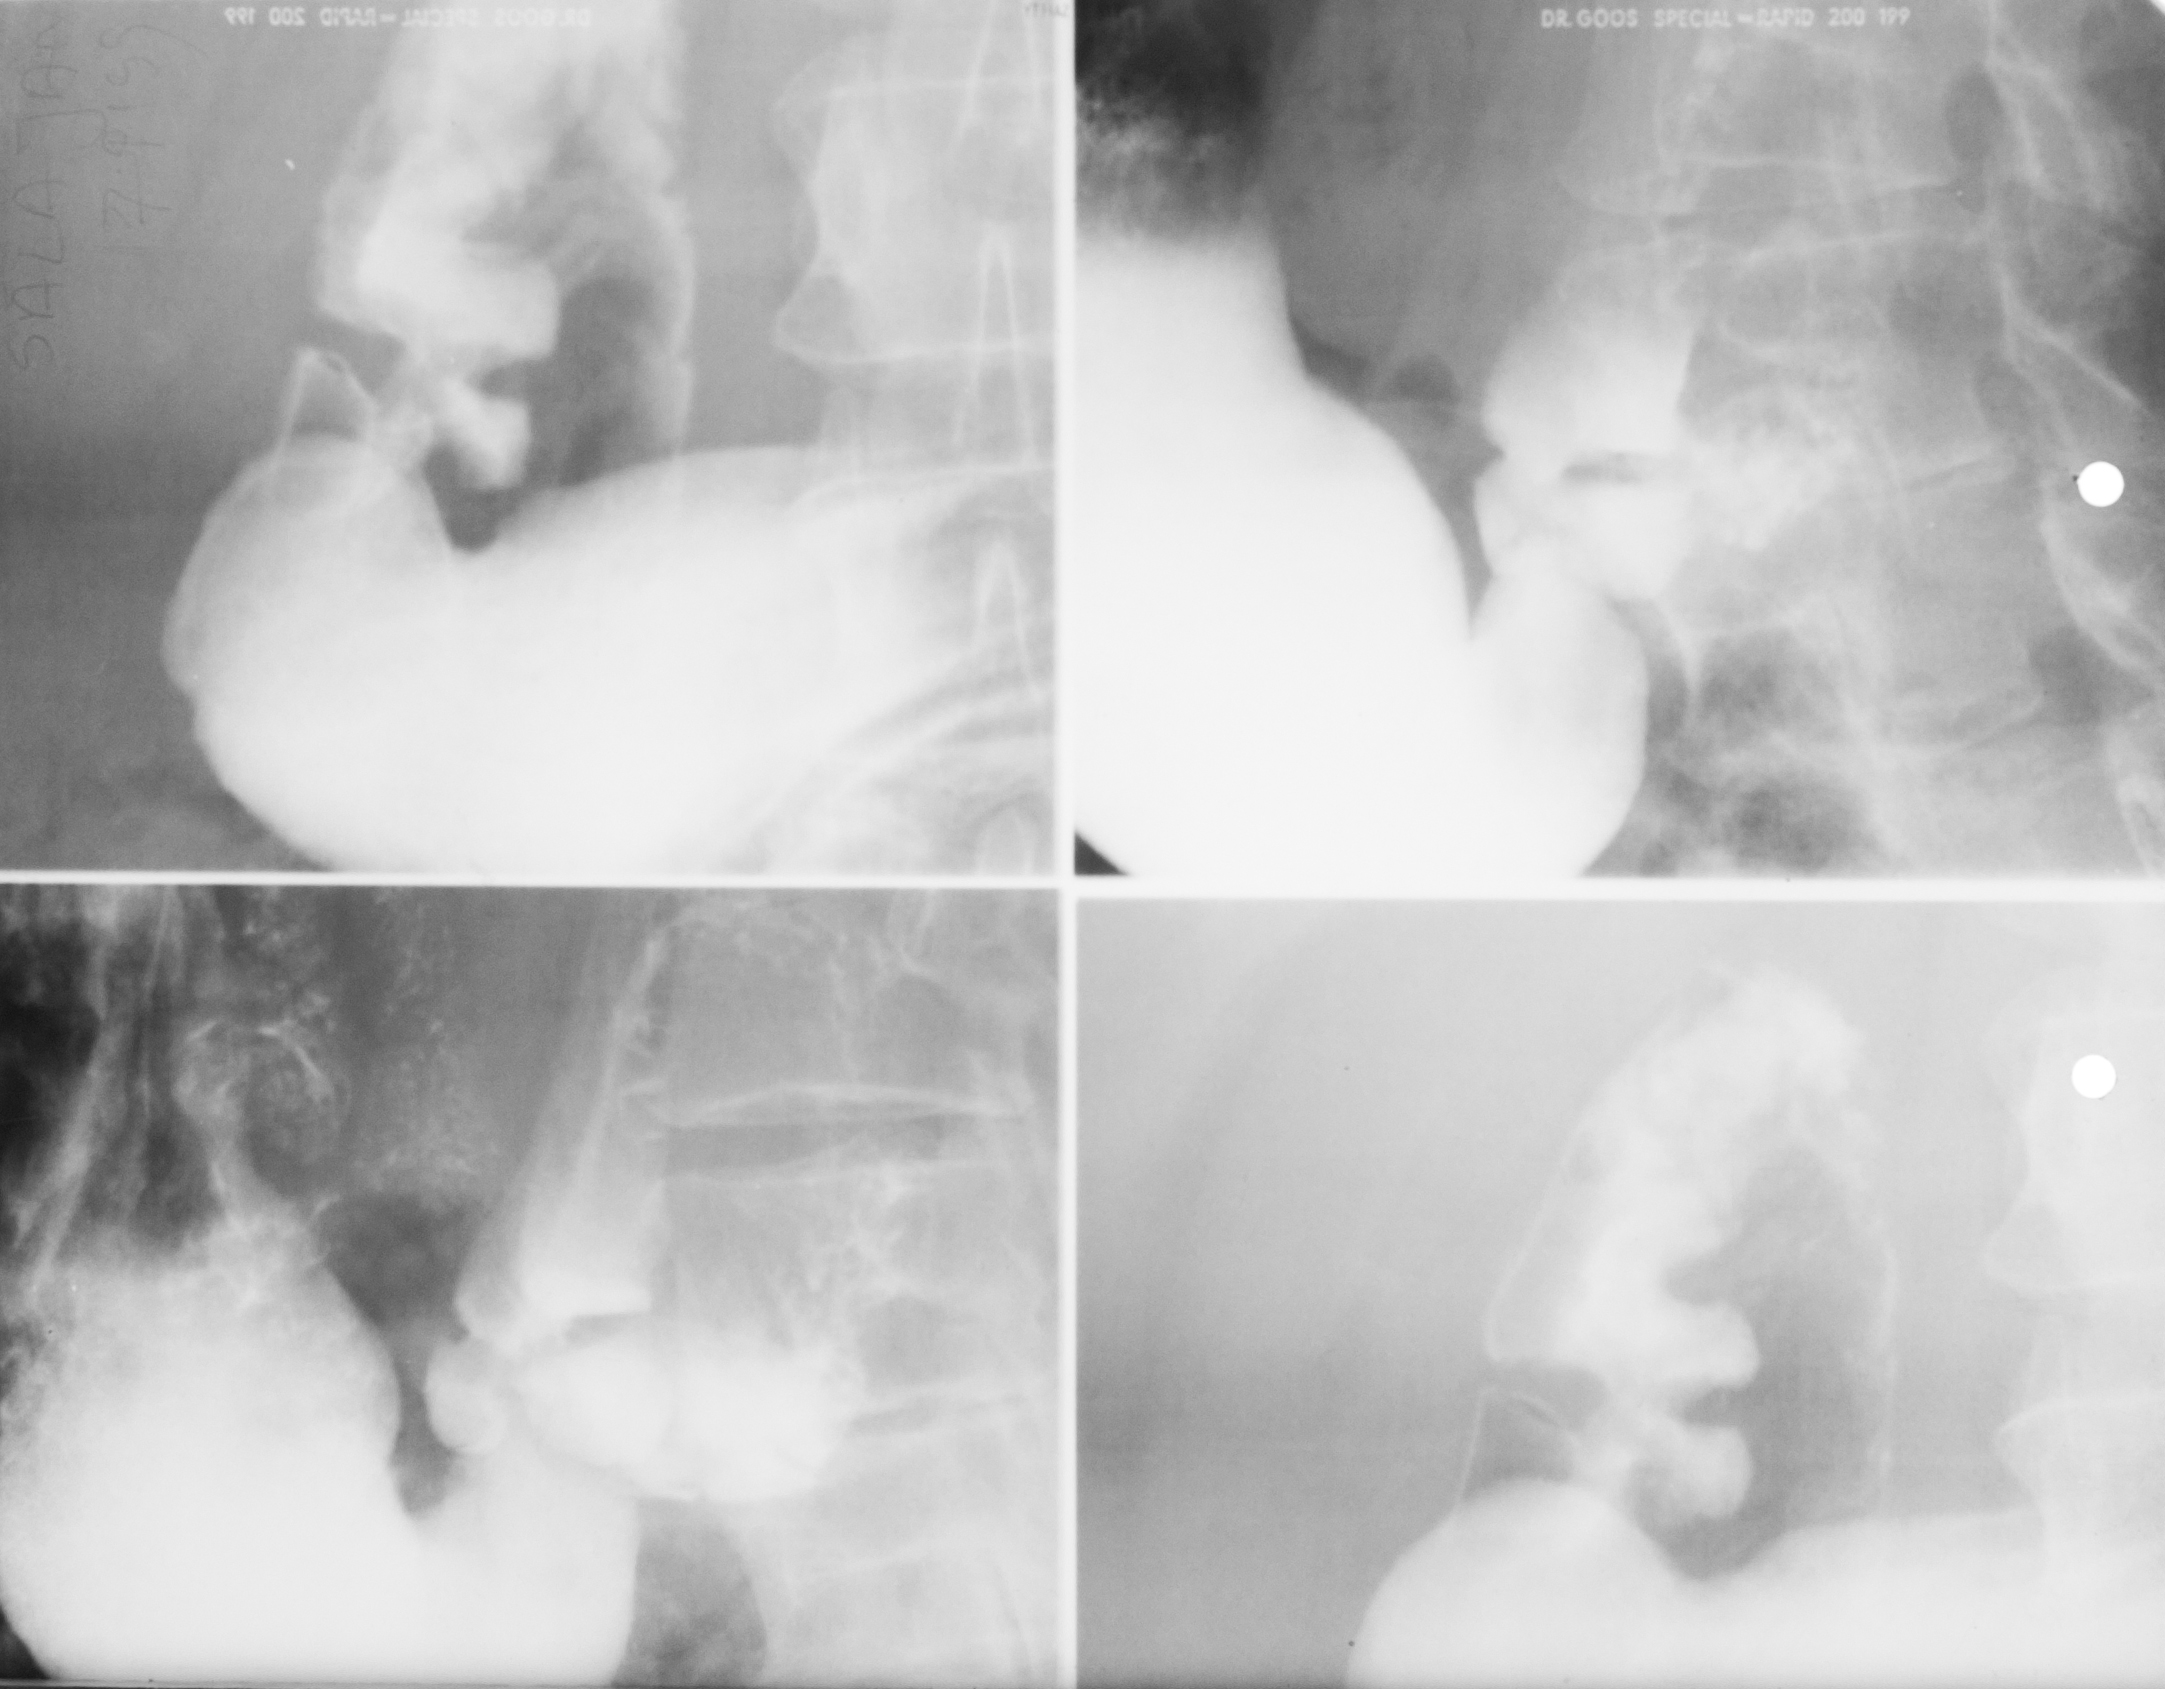

DIVERTICUL ESOFAGIAN

Tranzit baritat pe regiunea toracală

Se observă esofagul plus o imagine adiacentă a acestuia cu un camp de umplere,cu nivel orizontal și hipertransparență deasupra.

DIVERTICUL ESOFAGIAN

Tranzit baritat la nivelul esofagului.

Se observă o imagine de adiție(iese din conturul organului)

DIVERTICUL ZENKER

Tranzit baritat a esofagului pe radiografie de profil.

Se observă esofagul din profil,coloana vertebrală,imaginea de adiție cu substanță de contrast în interior și aer antidecliv

DIVERTICUL ZENKER( Văzut din față)

Pată persistentă de substanță de contrast,văzută din față,în proiecția mediastinului superior

STENOZĂ DE TIP BENIGN

Tranzit baritat la nivelul esofagului

Se observă o stenozare pe distanță mare,axială,simetrică a esofagului=Stenoză de tip benign.Se observă și o mica ulcerație:imagine de adiție triunghiulară la nivelul extremității superioare

STENOZĂ DE TIP MALIGN

Stenoză excentrică cu contur neregulat,pe o distanță mai mică

STENOZĂ DE TIP MALIGN

Contur neregulat,anfractous cu retrodilatare

Stenoză excentrică,nu este axială